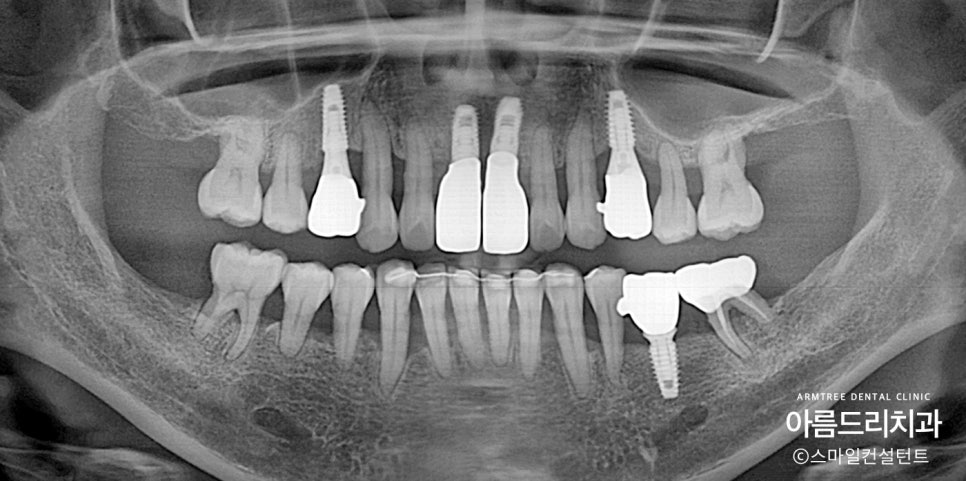

한참을 지난 후에 많이 좋지 않았던

위 양쪽 작은 어금니가

많이 흔들리기 시작했습니다.

애초에 뽑을지 고민했던 치아였는데

좀 더 사용하기로 했었던 치아입니다.

몇년 지나니 버티지 못했네요.

추가로 2개의 임플란트를 치료했습니다.

환자분의 경우 앞니 쪽에 뼈가 워낙 없어서

임플란트가 예쁘게 나오질 않습니다.

그렇지만 불행인지 다행인지

환자분은 활짝 웃어도 잇몸이 보이질 않아요.

이런 분들은 앞니가 예쁘게 나오지 않아도

임플란트 치료를 수월하게 진행할 수 있습니다.

만약에 잇몸이 훤히 보이는 분이셨다면

다른 치료방법을 고민했을 것입니다.

뼈이식, 잇몸이식, 핑크포셀린, 브릿지...

제 머리속이 복잡했겠지요.

다행히 복잡하지 않게 최대한 간단하게

치료를 마무리할 수 있었습니다.

남은 치아들 지속적으로 관리하는 게

가장 중요하기 때문에

앞으로도 쭉~~

아름드리치과 함께할 것입니다.